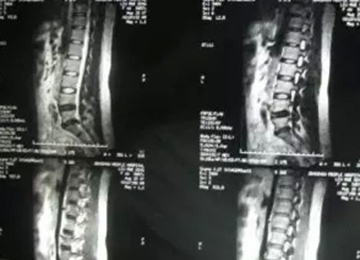

核磁矢状位

核磁轴位

2011年,小张(20岁),L4-5椎间盘脱出,高密人民医院、青岛山大医院要求手术。右腿外侧疼痛,迈不开步子,直腿抬高不过20°。